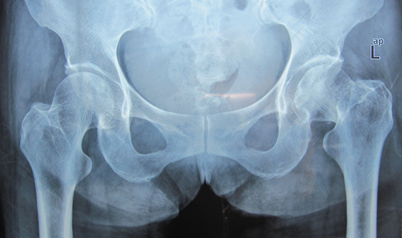

由于长期大量的饮酒而造成酒精在体内的蓄积,导致血脂增高和肝功能的损害,血脂的升高,造成了血液粘稠度的增高,血流速度减缓,使血液凝固性改变,因而可使血管堵塞,出血或脂肪栓塞,造成骨坏死,引起股骨头痛。同时外伤和激素使用,也是导致股骨头坏死发病的一个重要原因。

股骨头坏死在病情发展的期间会慢慢出现股骨头的塌陷,将会导致股骨头会完全溶解消失,且整个髋关节造成严重脱位,这时候病人就完全造成了伤残。所以股骨头坏死的患者不仅不能够自愈,还可能出现进行性加重。

针对股骨头坏死应该早做预防,发现股骨头坏死,抓紧时间治疗,在治疗股骨头坏死的过程中一定要避免负重。严格限制负重,要求患者扶双拐,甚至坐轮椅,这样才能够有效的缓解病情的进行性发展为降低治疗难度。